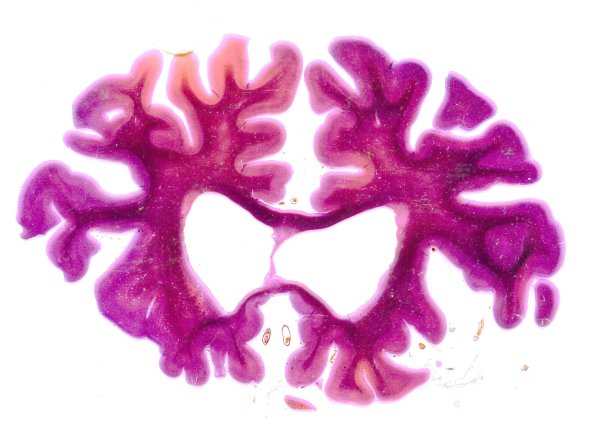

Washington University Experience | NEURODEGENERATION | Huntington Disease | 19A Huntington's Dz slab microtome section

Case 19 No History This case of HD was worked up using large histological glass plate sections that show marked caudate atrophy, cortical atrophy and hydrocephalus ex vacuo.